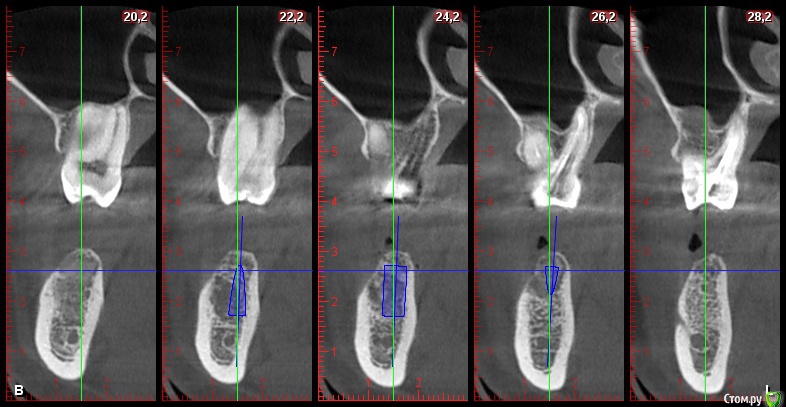

DenisV Опубликовано 22 мая, 2018 Поделиться Опубликовано 22 мая, 2018 Уважаемые коллеги, подскажите советом, допустимо ли с вестибулярной стороны 1.5мм кортикальной кости, или лучше НКР? на фото имплант 4.3*10? Ссылка на комментарий